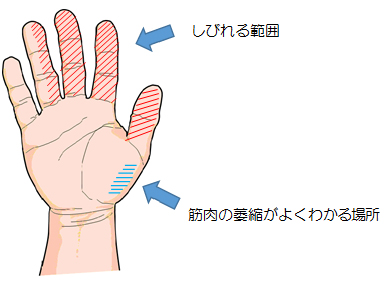

絞扼性末梢神経障害:手根管症候群

▶ 病状・特徴

母指、示指、中指、環指の母指側半分、手掌部にしびれを自覚します。しびれの出現する時間帯は様々で、作業中や夜間に自覚することや、常にしびれていることもあります。神経障害が進行するとつまむ動作に必要な母指手掌部の筋肉(母指球筋)が萎縮します。

▶ 病態

手首の掌側の手根管という管腔構造の中を、指を曲げる屈筋腱と正中神経が通っています。様々な原因で生じる腱鞘滑膜炎による腱、腱鞘の肥厚や骨の変形などにより手根管が狭くなることで正中神経が圧迫を受け、障害されます。神経の機能が低下すると手の自覚的なしびれ(安静時や夜間時)、感覚障害(触っている感じ、冷感、温感がわかりにくい、または逆に過敏に感じるなど)、運動障害(正中神経が支配している筋の萎縮)が生じます。特に重症になると親指の腹とその他の指の腹を合わせるつまみ動作(対立動作)が困難になります。